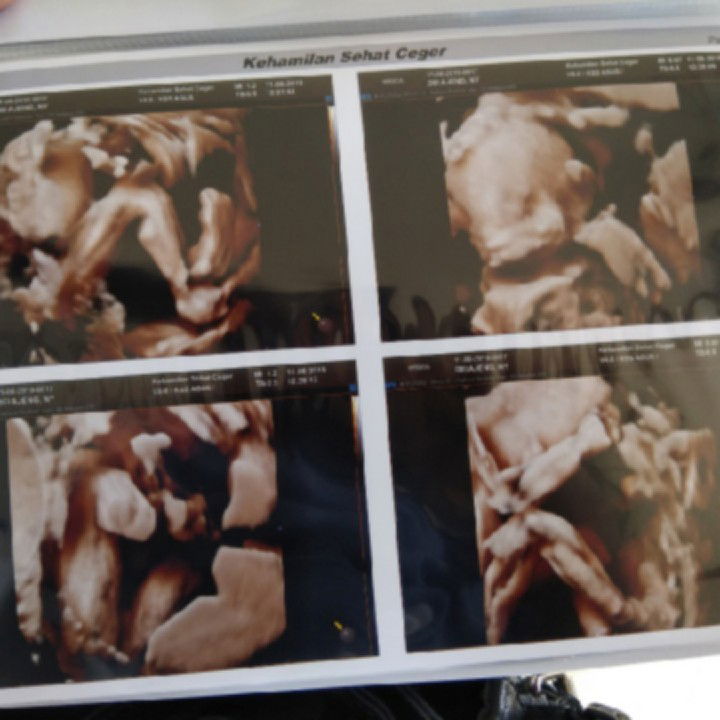

USG 4D

Bun kemarin aku USG 4D sempet takut, takut kalo dedeknya kenapa kenapa. Karna akunya masih bandel masih suka berpergian jauh masih suka makan pedes masih suka minum obat warung masih sering makan mie dan minum soda. Tapi pas kemarin USG liat si dedek yg alhamdulillah semuanya bagus semuanya normal jadi nangis aku. Posisi tangan dedek kayak ninju gt mungkin kalo akunya nakal dedek lgsg ninju perut biar aku sakit hahahahaha ?? bunda di sini udah ada yg tau jenis kelamin si dedek belum?